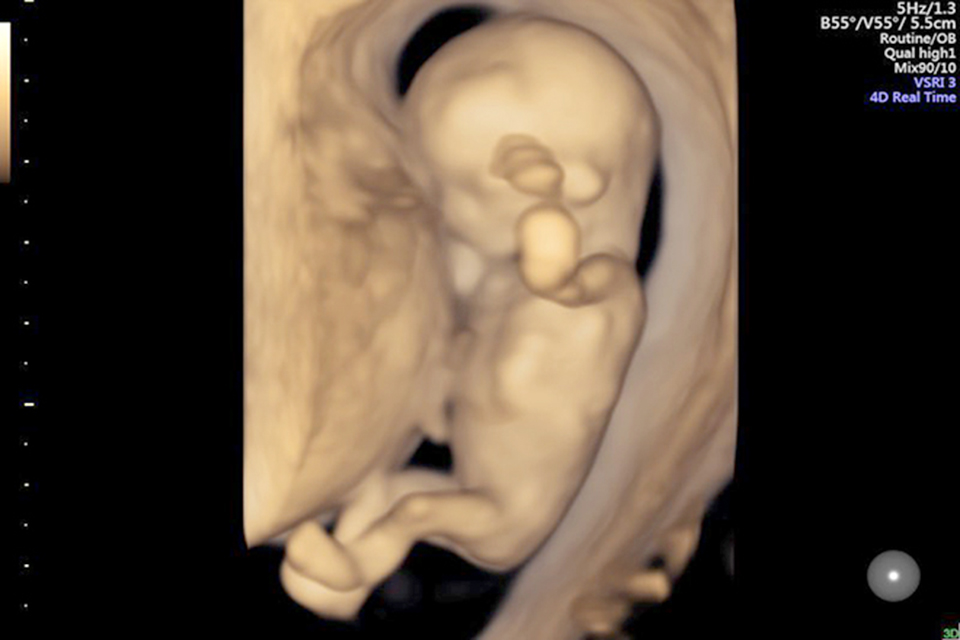

Khám thai 12 tuần mẹ sẽ thấy hình hài thai nhi ngày càng phát triển

Siêu âm 4D, 5D khi khám thai 12 tuần là thời điểm rất quan trọng để đo độ mờ da gáy. Nhờ phương pháp siêu âm 3 chiều hiện đại, các bác sĩ sẽ chẩn đoán chính xác hơn những bất thường nhiễm sắc thể mà thai nhi có thể mắc phải bao gồm dị tật tim, bị hội chứng Down hoặc dị dạng tứ chi,...

Ngoài ra, siêu âm 4D khi thai nhi 12 tuần còn giúp mẹ biết được các chỉ số siêu âm như tuổi thai, cân nặng, chiều dài của con, nhất là tính ngày dự sinh chính xác cũng như đưa ra những lời khuyên dinh dưỡng, cách ăn uống tốt cho cả hai mẹ con.

Siêu âm 4D, 5D khi khám thai 12 tuần là thời điểm rất quan trọng để đo độ mờ da gáy

Khi khám thai 12 tuần bằng siêu âm 4D, mẹ có thể thấy hình ảnh thai nhi có những cử động đáng yêu